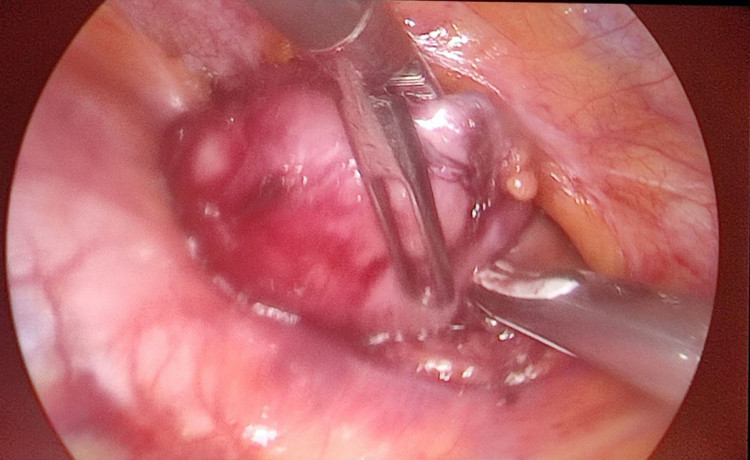

Qua các vết rạch nhỏ vào khoang màng phổi phải, phẫu thuật viên đưa dụng cụ nội soi vào tỉ mỉ phẫu tích, bóc tách và cắt toàn bộ tuyến ức kèm khối u. Sau khoảng hơn 30 phút thực hiện, toàn bộ tổ chức tuyến ức và khối u tuyến ức kích thước khá lớn đã được cắt bỏ hoàn toàn và lấy ra ngoài mà không gây mất máu.

| Hình ảnh khối u tuyến ức qua nội soi được kíp phẫu thuật bóc tách - ảnh BSCC |